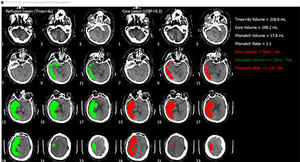

同製品を使った,CT画像の解析例

脳画像解析プログラム PMAneo(以下 PMAneo)は,MRI拡散強調画像から低ADC値領域を計測,またMRIまたはCT灌流画像からCBF,CBV,最大遅延時間を計測し,脳血流低下領域の容積およびこれらの差と比を算出,表示する,全自動脳画像解析ソフトウェア。

PMAneoは,虚血コアと低灌流領域に相当する体積及びミスマッチの自動解析を数分で行う脳画像解析プログラム。